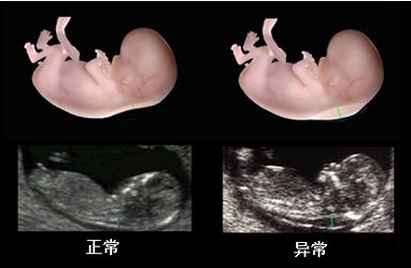

在线咨询系统彩超是筛查胎儿先天缺陷的重要方法,也是每位孕妈妈应该要做的产检项目之一。因此系统彩超的费用就成了孕妈妈们非常关注的问题,不少孕妈妈认为,系统彩超设备是一种先进的仪器,做系统彩超费用一定比较贵。那么,做系统彩超到底多少钱?

贵阳和谐阳光产科拥有经验丰富的超声科医师,擅长胎儿生长发育评估和胎儿畸形的诊断及胎盘病变的超声诊断。与产科医生无缝接力,对系统彩超的检测筛查准确率高,避免了因医院误诊、经验不足等原因导致孕妇流产、胎儿缺陷等问题。